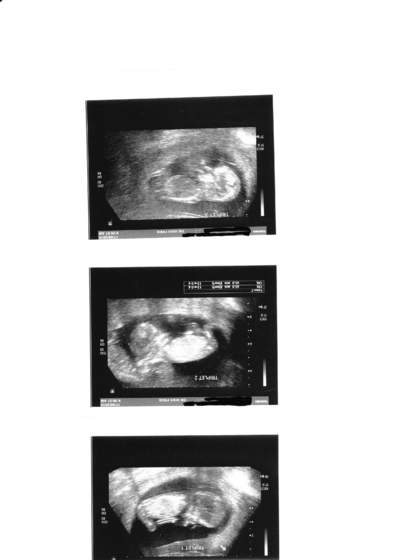

Akuku śliczny maluszek,Kuba w 11tc tak skakał że szok,nogami się odbijał,obracał,robił tak do prawie 30tc potem się uspokoił hehe ciasno zaczęło się robić hehe :-)